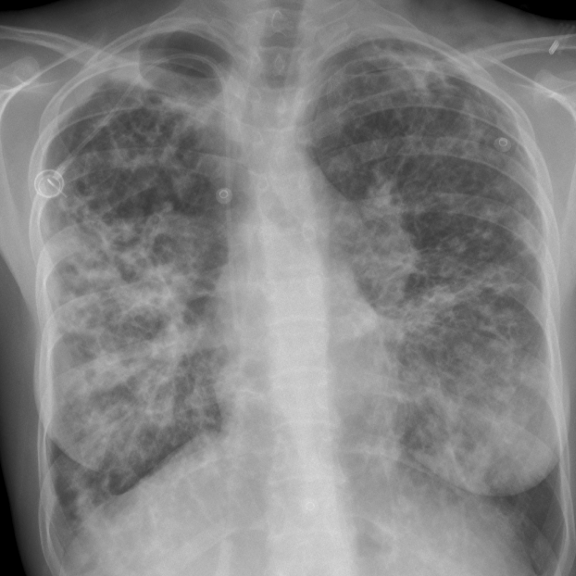

Syndrome Interstitiel

- Réticulaire

- Nodulaire

- Réticulo-Nodulaire